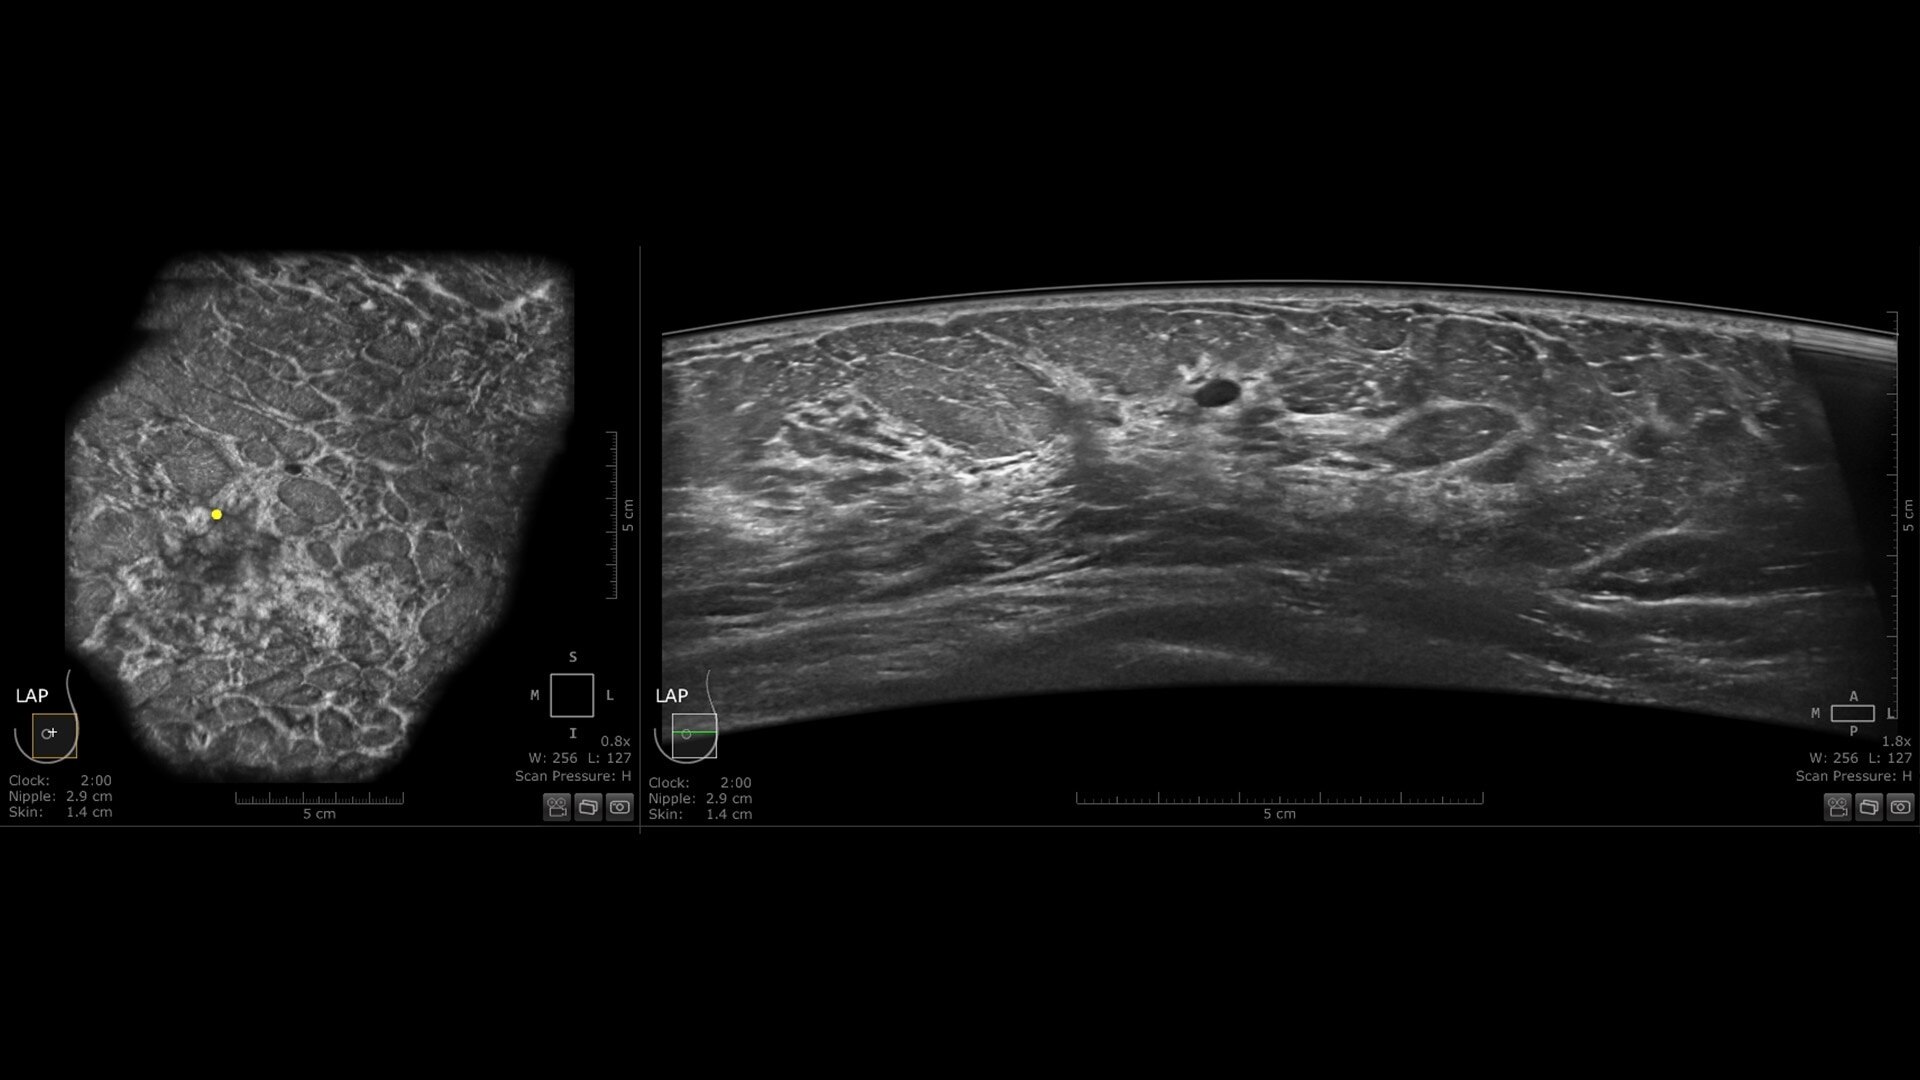

The novel Reverse Curve™ transducer is designed for enhanced performance

Its gentle 15.3 cm shape follows the breast's natural contour, enhancing patient comfort* and ensuring full contact for comprehensive coverage. The improved image quality* increases diagnostic confidence for reading ABUS exams.

s-curve-reverse-curve-transducer-desktop-ci-en